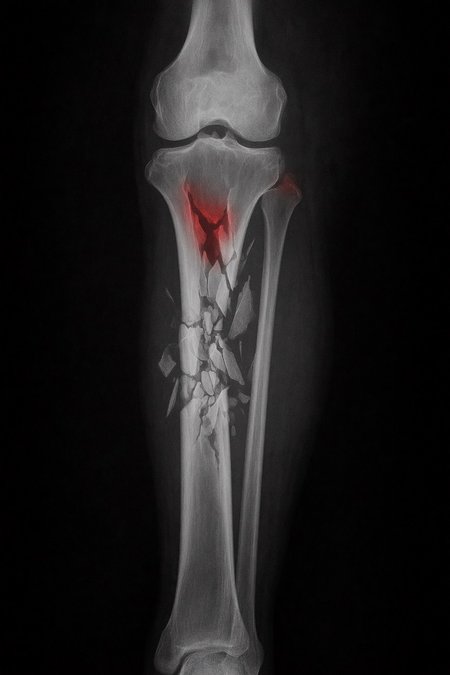

Can a model like Flux Kontext, designed for editing art and photography, be used to work with medical images, for example, with something 'as simple' as red-marking fractures?

The quick answer: it does do something interesting, but it over-scores and is far from reliable as a medical tool. It's a prototype to play with the idea, nothing more.

2. Ask: “Make marks where there is a fracture”.

Test results:

False positives ≈ 24%

Fracture detection ≈ 20%

Sensitive mode (more detection, lots of noise)

Euler, 15 steps, Karras

Denoise 1.0

Result:

False positives ≈ 80%

Fracture detection ≈ 86%

Even more aggressive settings (e.g. rk beta57 to denoise 1.0) reach the absurd: 100% false positives and 100% detection: it paints everything red and almost hits all fractures beyond marking healthy areas, for an untrained eye.